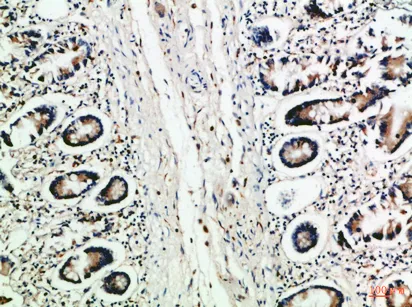

Reg IV Rabbit Polyclonal Antibody

Cat: APRab16998